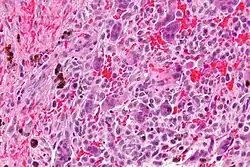

| Micrograph of a central giant cell granuloma showing the characteristic giant cells with surrounding cells that have nuclei that are dissimilar to those in the giant cells. H&E stain. | |

Histology of CGCG shows a lobulated mass composed of vascular connective tissue and multinucleated giant cells (osteoclasts). The giant cells may be diffusely located throughout the lesion or focally aggregate in the lesion, often clustered around hemorrhagic areas hemosiderin deposits. Lobules of the lesion can be separated by fibrous tissue or even thin layer of bone or osteoid that can be seen radiographically. Giant cells are thought to form in response to signals produced by fibroblasts and blood vessels or as a response to cytokines.[2][5]